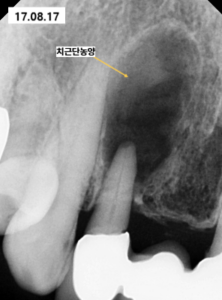

검사 결과 앞니 치아 뿌리 부위에 발생한

치근단농양의 크기가 치아 크기보다

더 크게 관찰될 정도로 매우 심한 상태였습니다.

먼저 신경치료를 통해 치아 내부의

감염원을 제거하고 치근단농양의 크기를

최대한 줄이는 과정을 진행하였습니다.